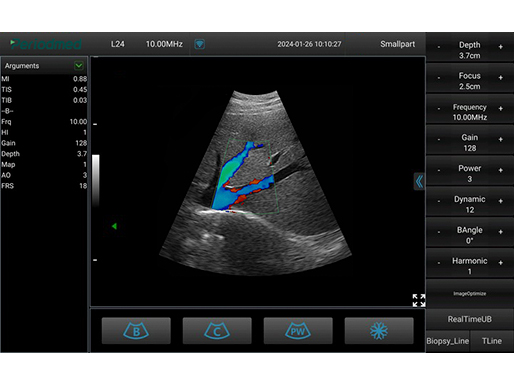

彩色模式 甲状腺

彩色模式 甲状腺

彩色模式 甲状腺